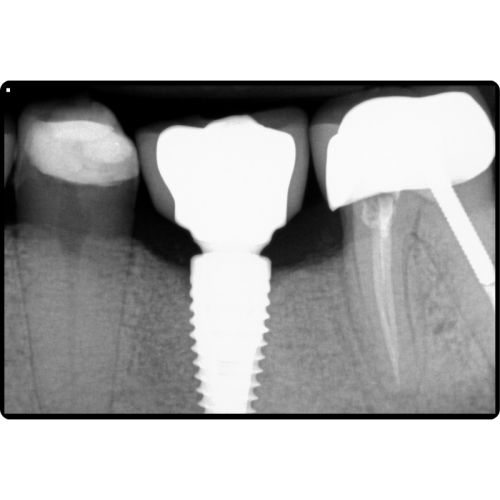

Dental Implants

Dental implants are the gold standard for replacing missing teeth. They provide a permanent, stable solution that looks, feels, and functions like natural teeth. Implant services include:

- Single-tooth implants

- Multiple implants

- Implant-supported crowns and bridges

Implants restore confidence, chewing ability, and long-term oral health.